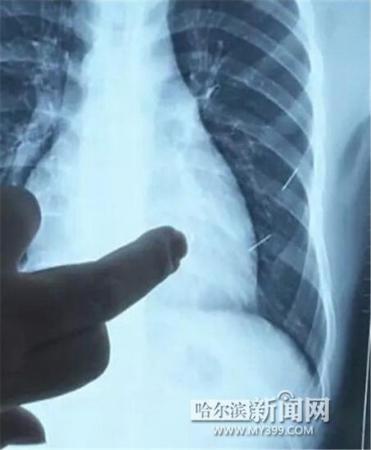

醫(yī)生指出X光片上的針狀物

昨日上午,記者在哈醫(yī)大二院第八住院部心外三病房找到了躺在病床上痛苦不堪的董立仁,家屬正在他身旁不斷安慰著他。見記者前來,董立仁母親李百燕拿出一張X光片,上面可以清晰地看到胸腔內(nèi)一共有4根針狀物,其中一根在心臟部位,兩根在胸腔壁上,還有一根在腹腔壁上。

心外三病房董立仁的主治醫(yī)生告訴記者,董立仁送到醫(yī)院時病情很危險,隨時可能危及生命?!巴ㄟ^檢查發(fā)現(xiàn),他心臟內(nèi)有一個金屬異物,正好在心臟上。心臟每次跳動都與其產(chǎn)生摩擦,導致出血,心包積液懷疑是血液。如果大量出血會凝結成血塊,血塊包裹住心臟就會影響心臟跳動,隨時都有停跳的危險。心臟上的異物是致命傷,其余胸腔壁和腹腔壁的異物傷害不大?!?/p>

昨天16時30分左右取針手術開始。因鋼針隨時會危及患者生命,此次手術定義為大型手術。開胸后,醫(yī)生打開董立仁心包,發(fā)現(xiàn)一枚鋼針已深深扎入心臟,僅露出1厘米長度在外。拔出鋼針后,醫(yī)生發(fā)現(xiàn),這枚針長達5厘米。受鋼針影響,心包出現(xiàn)大量積液,近800毫升。

隨后,在下胸壁位置,第二枚鋼針順利取出。在尋找另兩枚鋼針過程中,普外、胸外多名醫(yī)生也參與手術,為主刀醫(yī)生提供更為穩(wěn)妥的處理建議。根據(jù)X光片顯示位置,醫(yī)生未在患者體內(nèi)找到剩余兩枚鋼針。醫(yī)生懷疑,其中一枚鋼針可能深藏在肋骨骨膜位置,無法尋找,最后決定結束手術,做進一步觀察,研究下一次手術方案。